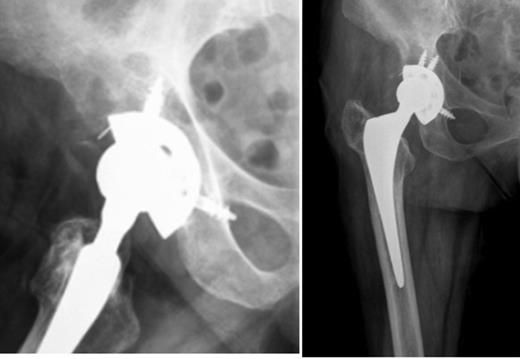

A 64-year-old woman presented with right hip pain of mixed characteristics with few months of evolution. She has had a fracture of the neck of the femur (Garden IV) after a fall nine years before, and undergone total hip arthroplasty with a cementless device (ART stem and ALIZE cup from Biomet, Warsaw, Indiana, USA). The patient followed our standard protocol for evaluation of pain after total hip arthroplasty, with plain radiographs and inflammatory markers (C-reactive protein and erythrocyte sedimentation rate). The inflammatory markers were within the normal range and comparing past and present radiographs there were signs of cup instability with osteolysis lines larger than 2 mm in zones I and II of De Lee and Charnley (Fig 1).

Right hip radiographs (lateral and AP) at the initial evaluation with osteolysis in zones I and II of De Lee and Charnley suggestive of cup loosening